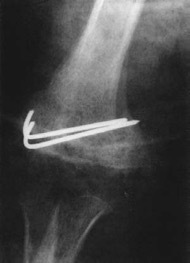

olecranon fracture Mx

undisplaced: immobilization and cast

displaced: surgery - tension band wiring or plate